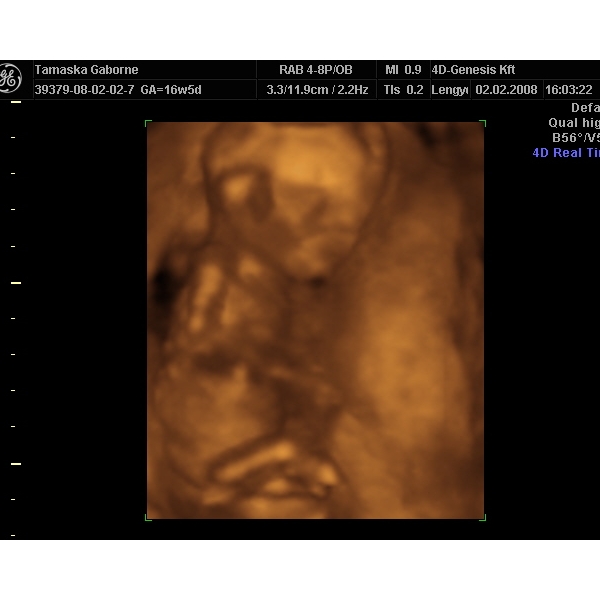

Mi még nem tudjuk, majd egy-két hét múlva belopódzom Anyuhoz egy potyaultrahangra, és megpróbáljuk kideríteni, mert a 30. heti uh-ig nem bírom ki

Jó az eü kapcsolat, mert ha akarok minden héten mehetek uh-ra.